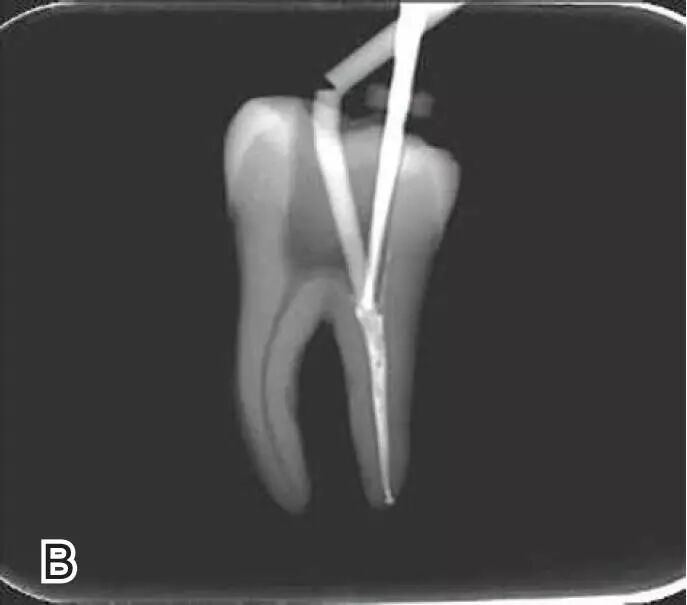

试尖

选择非标准牙胶尖(如0.04、0.06 锥度牙胶尖)作为主尖,型号一般与根管预备最大号的器械型号一致,能到达距根尖0.5~1 mm 处,主尖尖段与根管壁紧密接触。拍试尖X 线片进行确认。